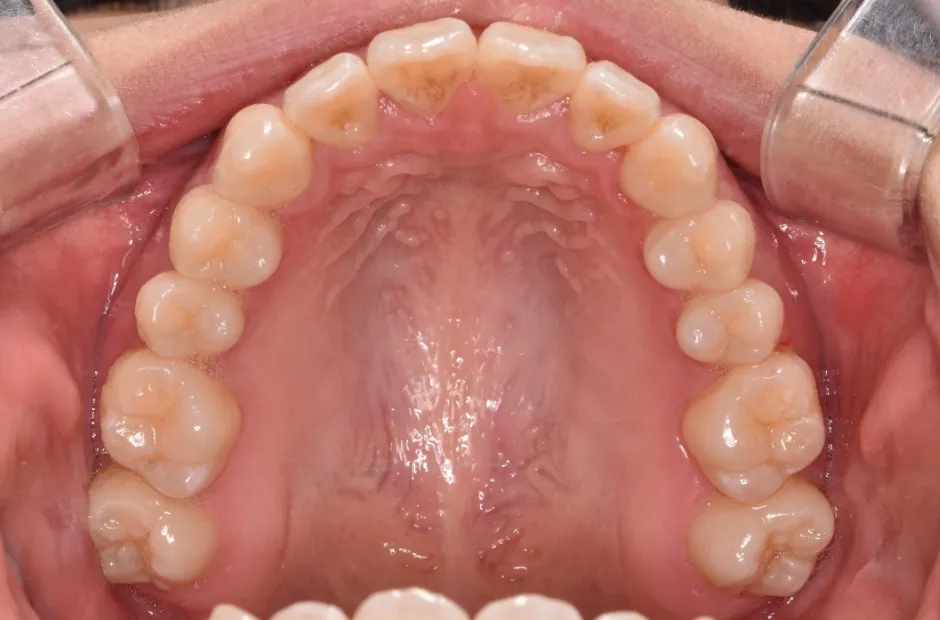

前歯部反対咬合

| 診断名・主訴 | 前歯部反対咬合 |

|---|---|

| 年齢・性別 | 14歳・男性 |

| 治療期間・回数 | 1年2か月 |

| 治療に用いた主な装置 | ブラケット矯正 |

| 抜歯部位 | なし |

| 治療費 | 60万円(税抜) |

| リスク・副作用 | 装置による違和感・疼痛・歯肉退縮・歯根吸収・虫歯のリスクなど |

治療前

治療後